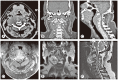

Anterior exposure for cervical chordomas remains challenging because of the anatomical complexities and the restoration of the dimensional balance of the atlanto-axial region. In this report, we describe and analyze the transmandibular transoral approach and multilevel spinal reconstruction for upper cervical chordomas. We report two cases of cervical chordomas (C2 and C2-C4) that were treated by marginal en bloc resection with a transmandibular approach and anterior-posterior multilevel spinal reconstruction/fixation. Both patients showed clinical improvement. Postoperative imaging was negative for any residual tumor and revealed adequate reconstruction and stabilization. Marginal resection requires more extensive exposure to allow the surgeon access to the entire pathology, as an inadequate tumor margin is the main factor that negatively affects the prognosis. Anterior and posterior reconstruction provides a rigid reconstruction that protects the medulla and decreases axial pain by properly stabilizing the cervical spine.